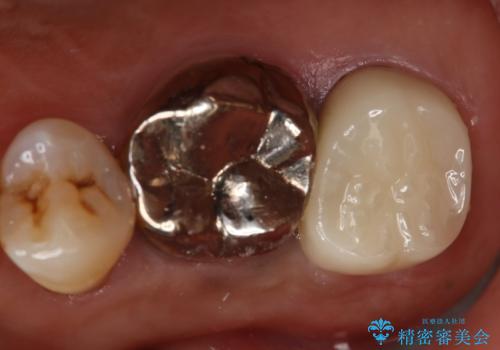

奥歯が取れた フルジルコニアクラウン

担当医 小澤俊哉